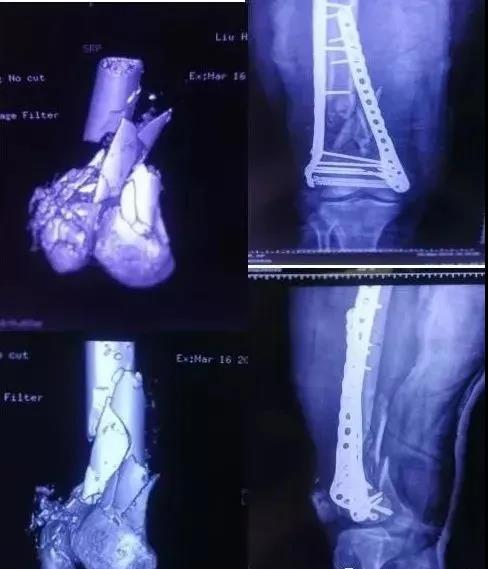

6)胫腓骨干骨折

- 皮包骨,应认识软组织覆盖的重要性。

- 8h之内,跟骨牵引,或者石膏托。

- 开放性骨折首选外支架。

- 2周软组织条件恢复,可以改内固定。

7)胫骨远端(pilon,踝部)

- pilon骨折,高能损伤,6-8h肿胀未形成,可以急诊做,手术时间<3小时。

- 10-14天,分步延期手术策略。

- 踝部骨折手术时机同样取决于皮肤条件。